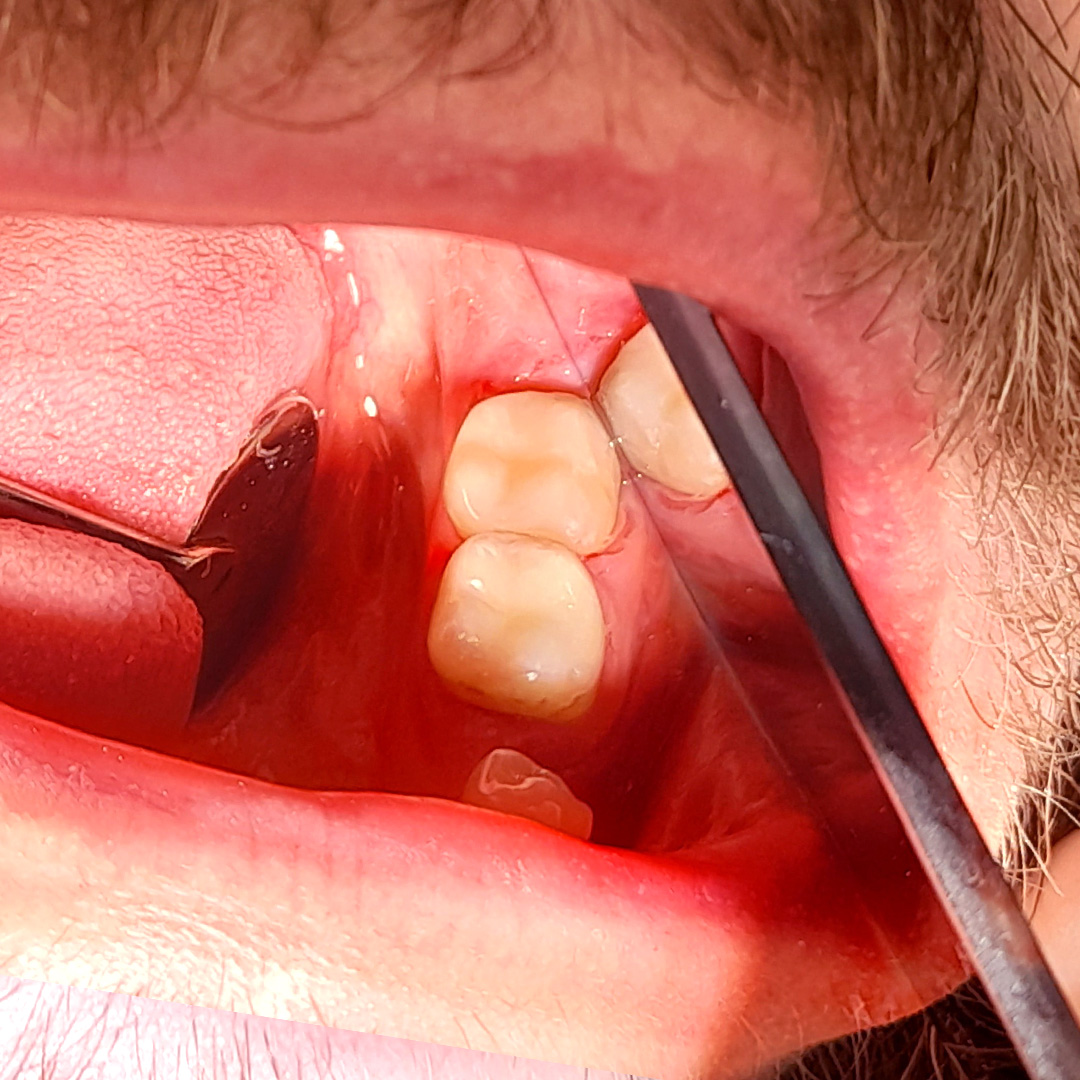

До и после лечения

В «Стоматологию Комфорта» обратился пациент с жалобами на наличие кариозных полостей и кратковременную боль от холодного в области 37 и 38 зубов. Терапевт Похилько Надежда Геннадьевна в ходе осмотра выявила кариозные поражения на окклюзионной и вестибулярной поверхностях 37 зуба, а также на окклюзионной и мезиальной поверхностях 38 зуба. Зондирование было болезненным. После препарирования полостей под контролем кариес-маркера, врачом был поставлен диагноз: глубокий кариес 37 и 38 зуба. Было принято решение о лечении с дальнейшей постановкой пломб из композита светового отверждения Estelite.

- постановка пломб из композита Estelite.